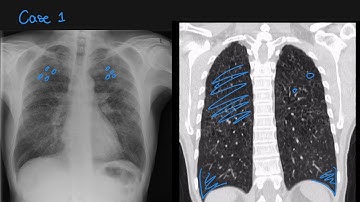

Lung Disease Prediction from Chest X Rays